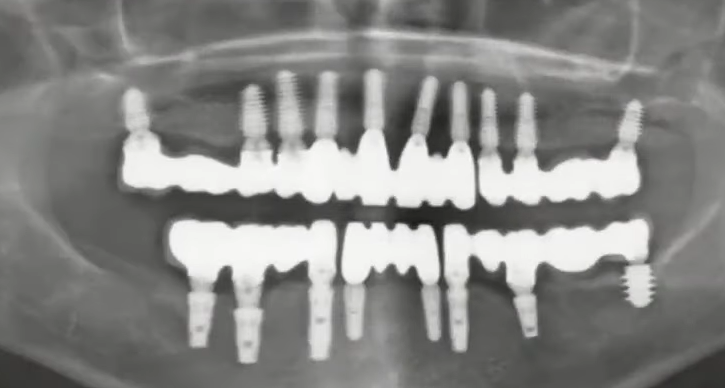

The following photo shows a restoration 9 years post-op, and the bone level around the implants has remained virtually unchanged. Several factors were at play here:

- Correct load distribution: The upper jaw is divided into 4 bridges and has a sufficient number of implants (10 units).

- Sufficient bone volume between the implants: A distance of at least 3 mm ensures good blood supply to the bone tissue, which is crucial for long-term stability, as confirmed by this image.

- The right choice of implant design: The implants are well integrated, and this restoration can last for many more years without significant changes.

An example of a successful restoration with minimal bone loss around the implants 9 years after implant placement. YouTube / Dr. Kamil Khabiev / Dental Guru Academy